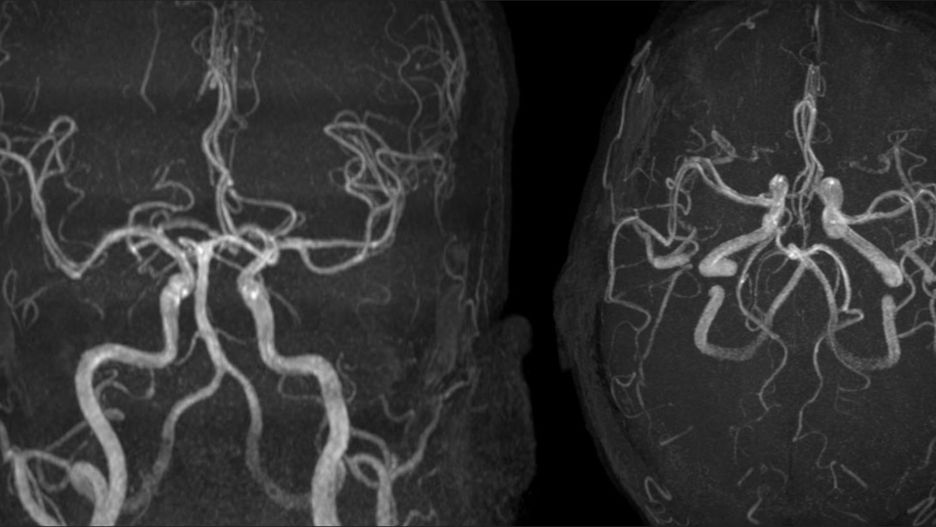

Cechy kliniczne i neuroradiograficzne leukoencefalopatii wywołanej wdychaniem fentanyluCechy kliniczne i neuroradiograficzne leukoencefalopatii wywołanej wdychaniem fentanylu

Źródło zdjęć: © casereports.bmj.com

Przypadek Amerykanina jest pierwszym zgłoszonym przypadkiem toksycznej leukoencefalopatii, czyli uszkodzenia istoty białej mózgu. Lekarze nie mają wątpliwości, że jest to wynik palenia fentanylu. Już wcześniej badacze dysponowali dowodami na to, że do leukoencefalopatii prowadzi palenie heroiny, przyjmowanie niektórych leków immunosupresyjnych, czy chemioterapia.

W przypadku 47-letniego Amerykanina doszło do uszkodzenia dwóch struktur w mózgu. Ucierpiał jego móżdżek oraz istota biała. W chwili odnalezienia mężczyzna nie reagował i wymagał intensywnego leczenia szpitalnego. Był hospitalizowany przez 26 dni, po czym został przeniesiony do specjalistycznej placówki opiekuńczej na kolejny miesiąc, następnie wypisano go do domu.